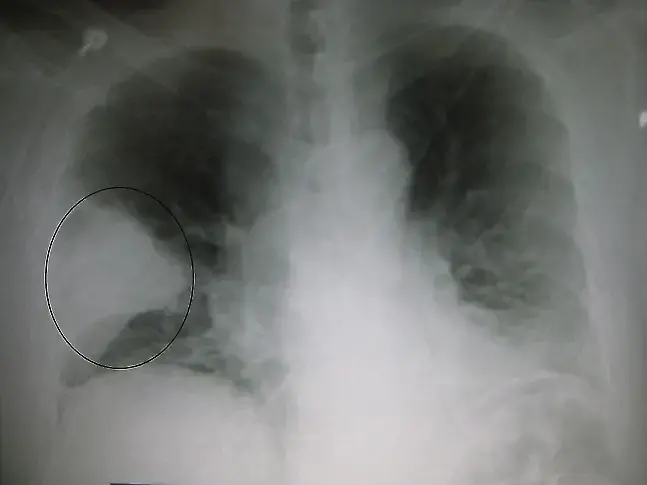

Пневмонията е възпалително заболяване на белите дробове, при което се нарушава нормалния процес на дишане. Тя винаги трябва да се счита за сериозно заболяване, независимо че при наличие на мощни антибактериални средства, най-често се изкарва "на крак". В зависимост от защитните сили на организма, придружаващите заболявания и възрастта тежестта на протичане варира от почти безсимптомни форми, до тежка дихателна недостатъчност с опасност за живота на болния.